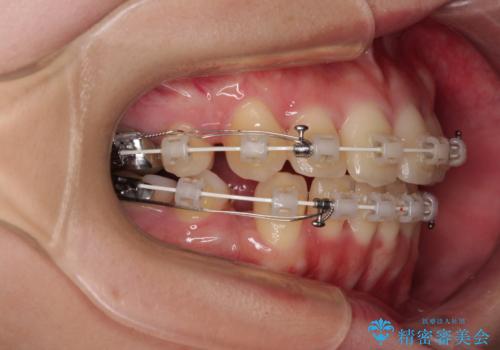

前歯のデコボコを抜歯矯正でスッキリした口元に

- 八重歯やクロスバイトを気にして来院された患者様です。

口元の突出感はありませんでしたが、デコボコが強く、非抜歯矯正とすると出っ歯仕上がりとなる可能性があったため、上下左右の第一小臼歯4本を抜歯し、ワイヤー装置にて矯正治療を行うこととしました。

デコボコがスッキリするだけでなく、口元の突出感も少し改善され、満足のいく仕上がりとなりました。